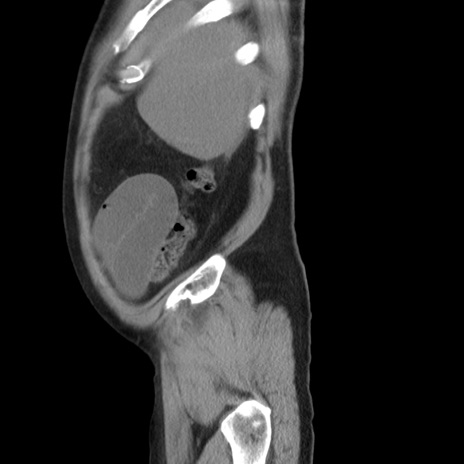

症例20(矢状断像)

【症例】 60歳代男性

【主訴】 腹部膨満、嘔吐

【現病歴】5日前頃より倦怠感を認め食事量減少し4日前の朝嘔吐、食事摂取困難となった。 3日前近医受診し点滴施行され整腸剤などを処方された。 当日他院を受診し、腹部膨満著明、炎症反応の上昇(CRP10.8、WBC11200)あり、紹介受診となる。

【身体所見】 意識JCS1 受け答えがはっきりしないBP 111/57mHg、 P 67bpm、、BT35.2°C、SpO2 97%(RA)、 腹部:膨隆、打診で鼓音あり、全体的に圧痛有り、腸蠕動音(-)、反跳痛ははっきりせず。

【データ】WBC 11400、CRP 14.20